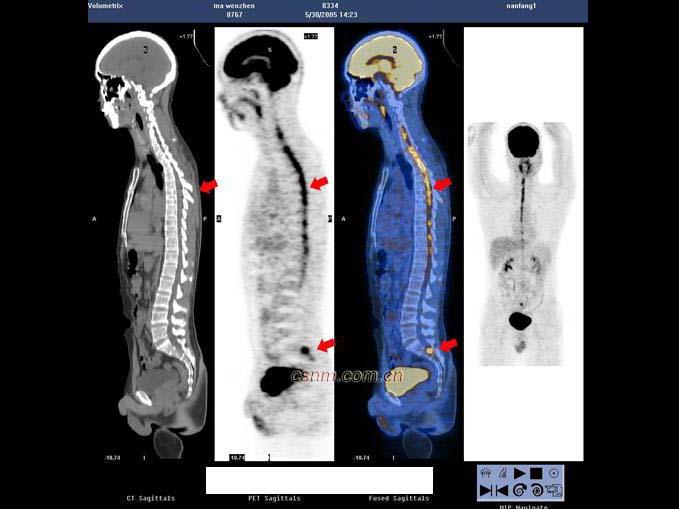

[单选题]男,32岁,确诊左颞叶胶质母细胞瘤Ⅳ级,手术切除病灶,术后放疗2个月,化疗3个疗程;现距放疗结束17个月。查体:右上肢轻度乏力,骶尾部及双足麻木,排便困难;检查:MRI示左颞叶肿瘤局部复发可能。行PET/CT显像全身检查如图。最可能的诊断 ( )A.左侧颞叶术后瘢痕组织改变B.左侧颞叶肿瘤复发C.恶性肿瘤沿椎管种植性转移D.马尾种植性转移灶E.以上都不是

[多选题] 男,32岁,确诊左颞叶胶质母细胞瘤Ⅳ级,手术切除病灶,术后放疗2个月,化疗3个疗程;现距放疗结束17个月。查体:右上肢轻度乏力,骶尾部及双足麻木,排便困难;检查:MRI示左颞叶肿瘤局部复发可能。行PET/CT显像全身检查如图。最可能的诊断()。A . 左侧颞叶术后瘢痕组织改变B . 左侧颞叶肿瘤复发C . 恶性肿瘤沿椎管种植性转移D . 马尾种植性转移灶E . 以上都不是